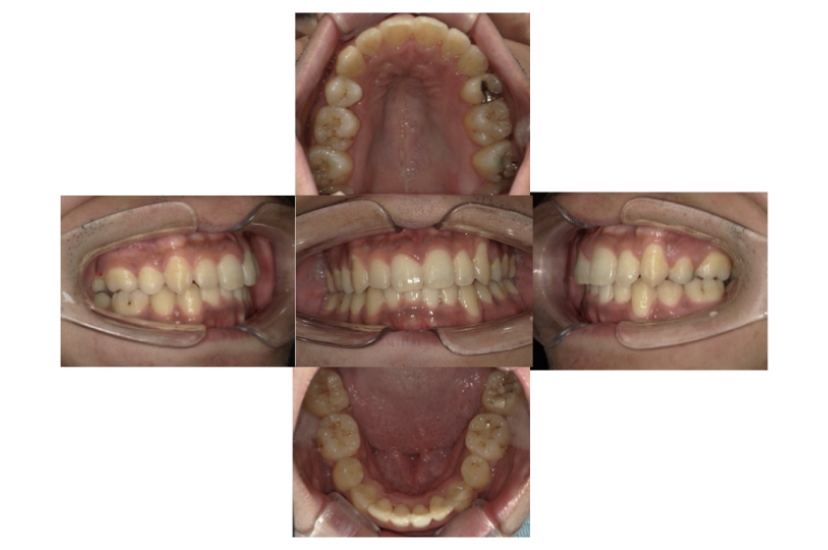

AFTER

上下顎叢生(上下の前歯のガタガタ)のケースです。

装置はラビアル(上下表側)で、上下顎の小臼歯を4本抜歯を行っています。抜歯したスペースを利用し、上下の前歯の後方移動と叢生(ガタガタ)の改善を行っています。口元の出っ張りを改善するため、歯科用アンカースクリューを使用して前歯の後方移動を行いました。

主訴 上下の前歯のガタガタを治したい。 口元を引っ込ませたい。

年齢・性別 22歳 女性

お住まいの地域 東京都大田区

治療方針 抜歯スペースを利用して上下前歯の叢生(ガタガタ)の改善

抜歯部位 上下顎左右第一小臼歯

使用装置 ラビアル(上下表側)、顎間ゴム、歯科用アンカースクリュー

治療期間 2年1か月

治療回数 20回

リテーナー クリアリテーナー